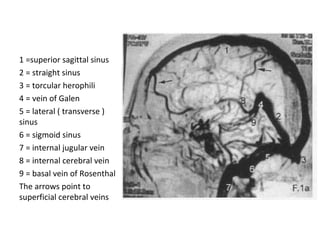

1 =superior sagittal sinus

2 = straight sinus

3 = torcular herophili

4 = vein of Galen

5 = lateral ( transverse )

sinus

6 = sigmoid sinus

7 = internal jugular vein

8 = internal cerebral vein

9 = basal vein of Rosenthal

The arrows point to

superficial cerebral veins